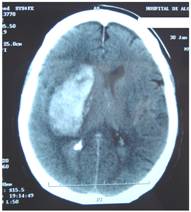

Figure 4 represents and example of ischemic stroke and hemorrhagic stroke on baseline and delayed CT with edema developing after 48 hours.

FIGURE 4

A. Ischemic stroke presenting with left hemiparesis. Normal CT on admission. CRP level: 6.9 m/dL; NT-PBNP level: 21pmol/L. B. CT scan after 48hours. Large infarction in the MCA territory showing mass-effect. CRP level: 7.9 mg/dL; NT-PBNP level: 139 pmol/L.